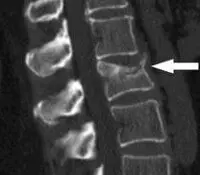

Остеопороз

У немолодих людей пекучий біль між лопатками і в грудному відділі хребта може бути викликаний остеопорозом, а також компресійним переломом тіл хребців.

При остеопорозі можуть боліти переломи ребер, які також можуть давати біль між лопатками і в міжхребтових областях.